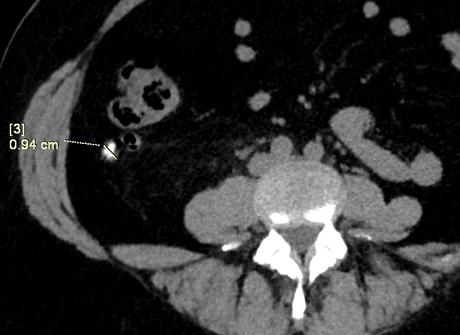

Se realiza búsqueda intencionada de la región de fosa iliaca derecha, apreciando una imagen tubular, en fondo de saco de ciego y presenta estriación de la grasa periapendicular la cual mide 10 mm en sentido anteroposterior, con presencia de un apendiculito en su interior de 5 mm, con densidad de 279 UH.